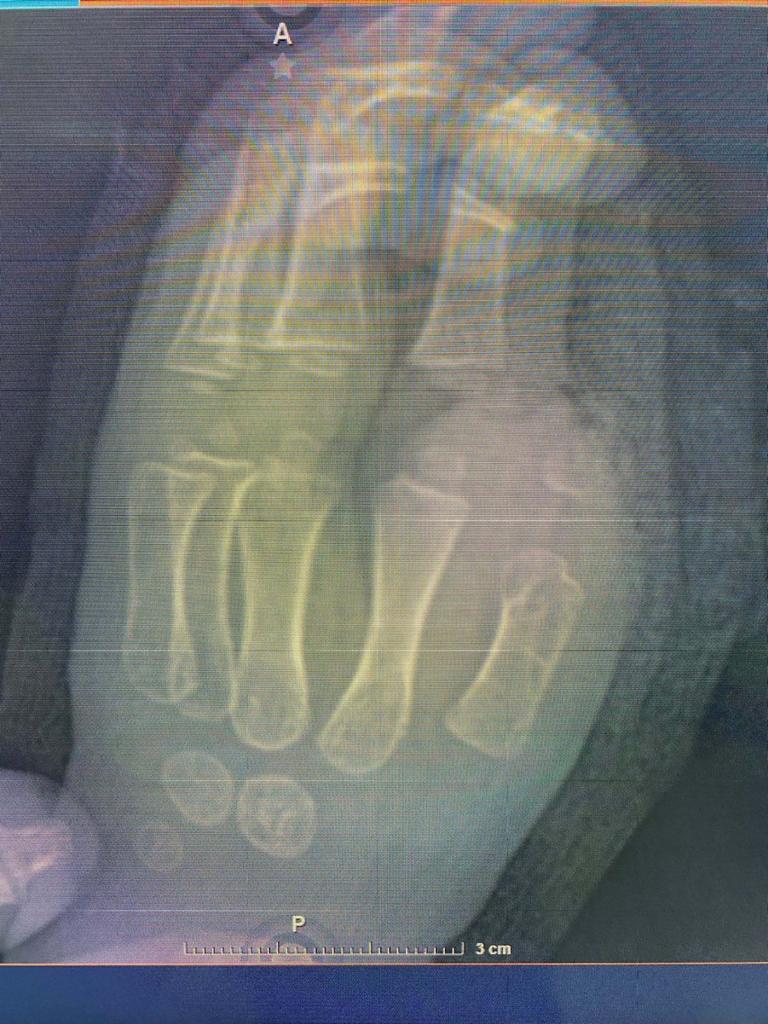

Monterrey.- Luego de que un abanico metálico le arrancara el dedo pulgar a un niño de 1 año 8 meses, cirujanos de la Unidad Médica de Alta Especialidad (UMAE) Hospital de Traumatología y Ortopedia No. 21, del Instituto Mexicano del Seguro Social (IMSS) en Nuevo León, reimplantaron con éxito la extremidad al menor, quien recuperará la funcionalidad de su mano izquierda casi al 100 por ciento.

Para reimplantarlo, el equipo de Cirugía Plástica reconstructiva del Hospital de Traumatología y Ortopedia, encabezado por el doctor Miguel de la Parra Márquez, tuvo que unir arterias, venas, tendones, hueso y nervios con suturas milimétricas, lo que implicó un proceso quirúrgico de alta complejidad.

El procedimiento, llamado supramicrocirugía, se realizó con el uso de microscopio al máximo aumento, las suturas fueron ultrafinas con un hilo transparente y tan delgado que prácticamente flota en el aire.

El trabajo quirúrgico duró seis horas y se realizó contra reloj, pues el miembro desprendido se encontraba en una hielera, envuelto en gasas húmedas, entre agua y hielo para su preservación por un tiempo máximo de 24 horas.